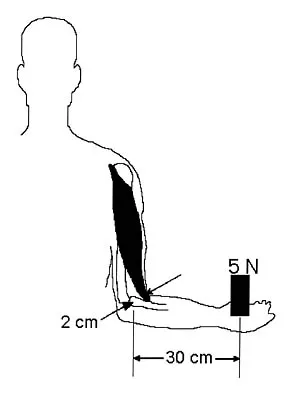

During the anterior approach for repair of a distal biceps tendon rupture, what structure, shown under the scissors in Figure 6, is at risk for injury?